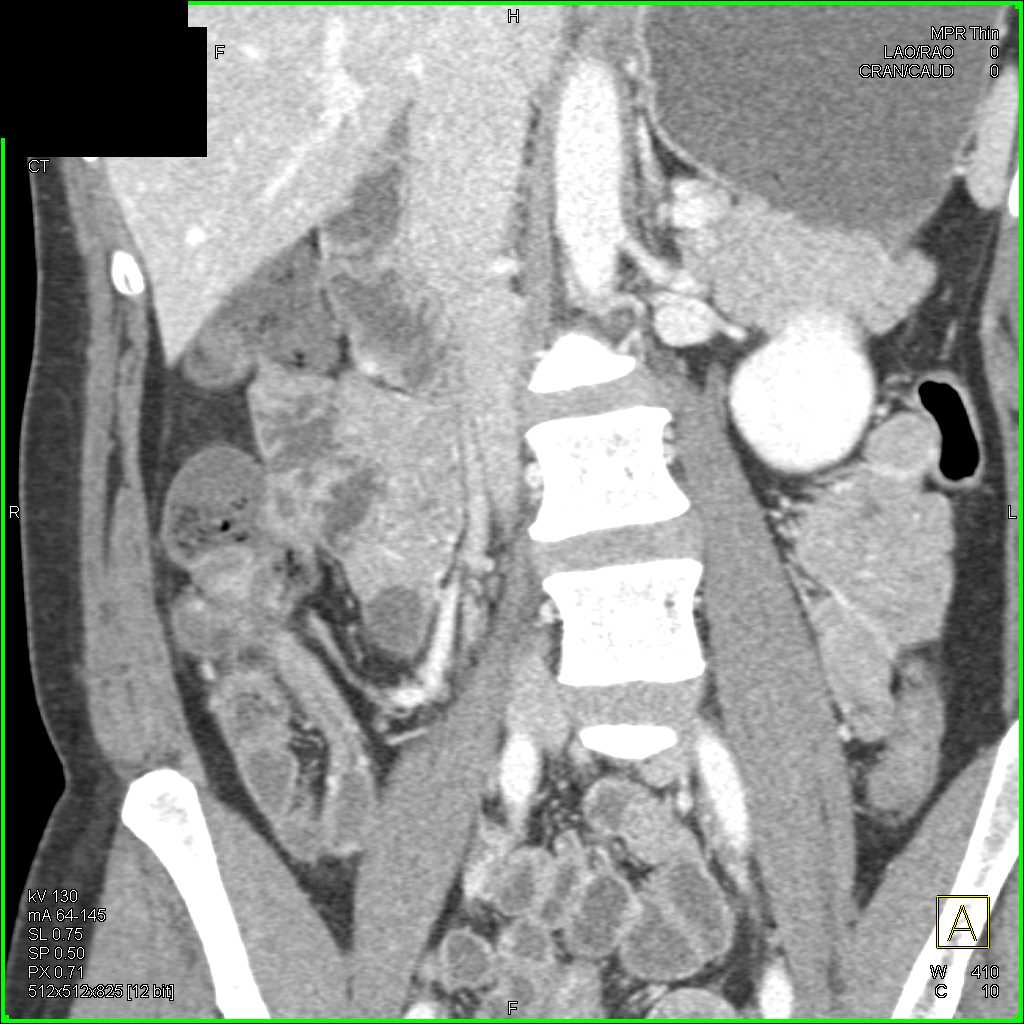

Crohns Disease Terminal Ileum